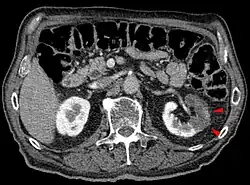

CT scan of the abdomen showing partial infarct of the left kidney.